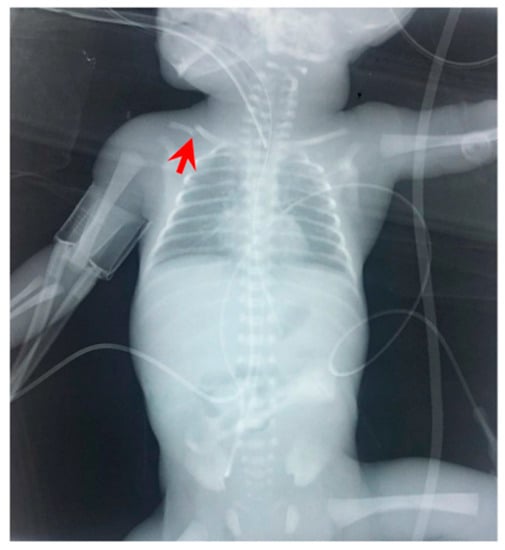

Figure 3.

Radiography of the neonate on the day of deterioration. Non-specific signal characteristics in the abdomen, such as distention and poor distribution of bowel gas. A clavicular fracture clavicle is noted on the right (red arrowhead).

Figure 6.

Radiography of the infant on the day of deterioration, with non-specific signal characteristics in abdomen, such as distended abdomen and poor distribution of bowel gas.

Figure 9.

(a) Chest and abdominal radiography depicting the abnormal position of umbilical venous catheter in the liver (red arrowhead); and (b) chest and abdominal radiography depicting air in the branches of right portal vein and hepatic parenchyma (red arrowhead).